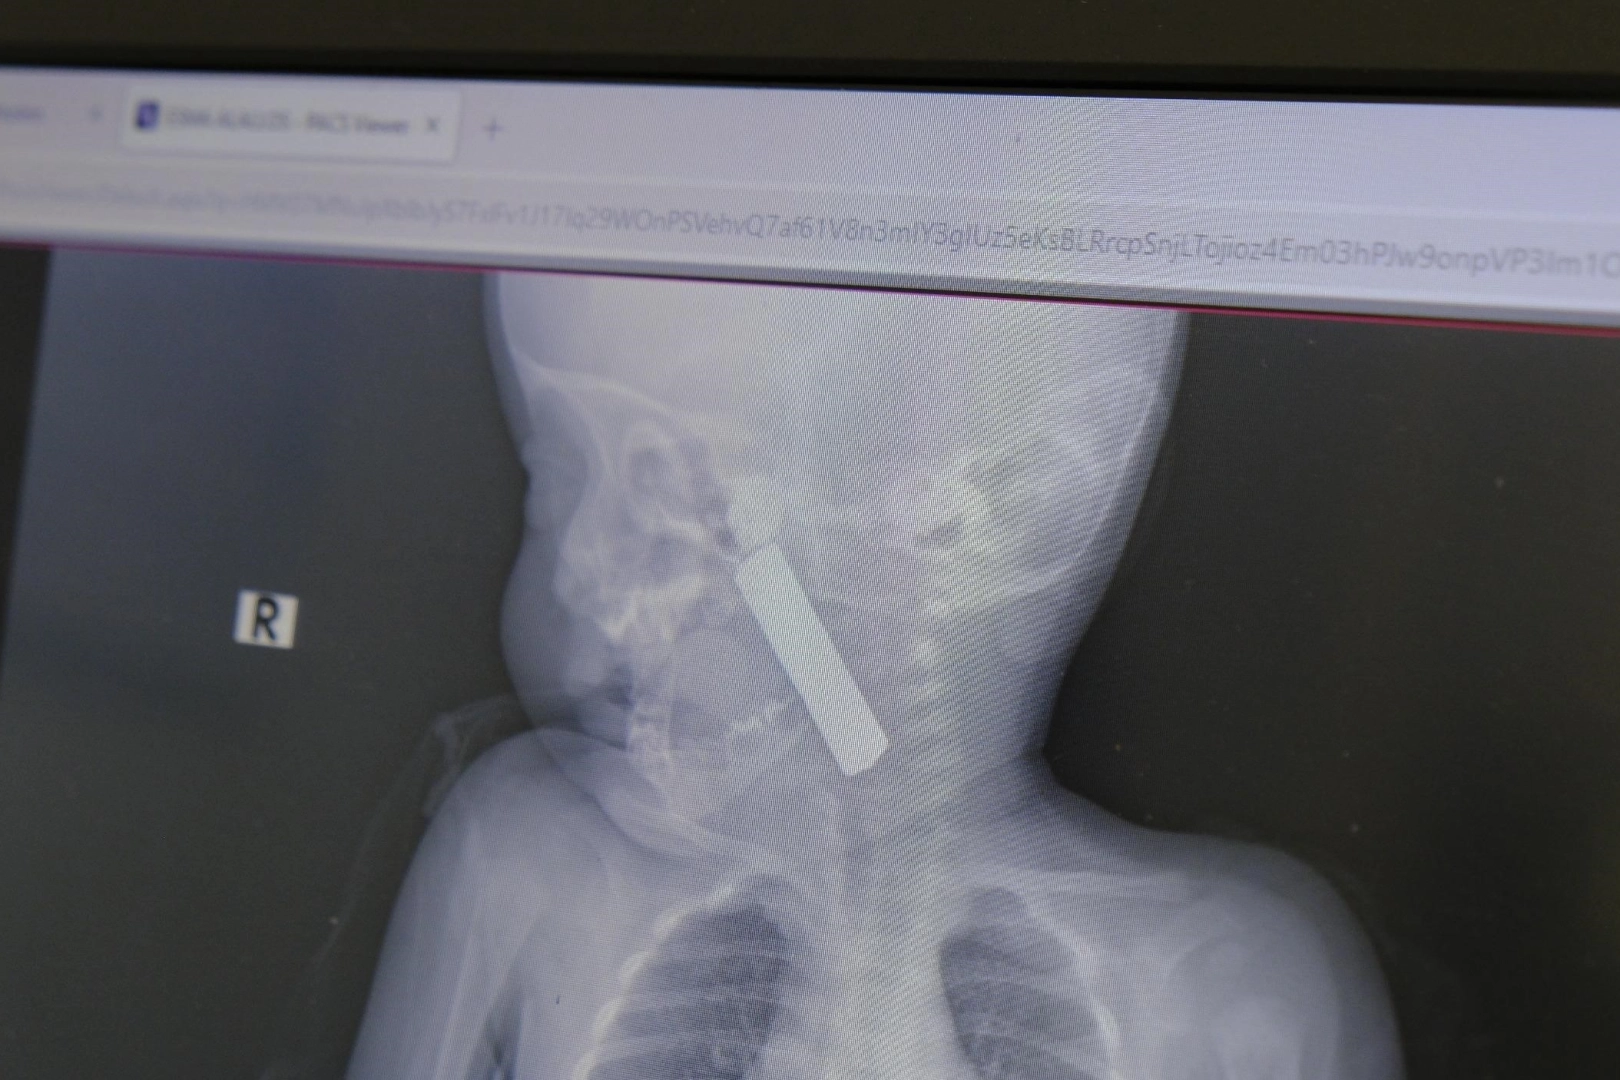

Edinilen bilgiye göre, Karaman’da yaşayan bir aile 6 aylık bebekleri E.A.’yı kusma ve nefes almada zorlanma şikayetiyle Karaman Eğitim ve Araştırma Hastanesi’ne getirdi. Acil serviste yapılan ilk müdahale ve tetkikler sonucunda, bebeğin boğazına yabancı bir cisim kaçtığı tespit edildi. Çekilen röntgen ve yapılan detaylı muayenede, boğazın alt kısmında kumanda pili olduğu ortaya çıktı.

Ameliyat sonrası açıklama yapan Doç. Dr. Uysal, şu bilgileri verdi: “Hastamızı gördüğümüzde siyanotik durumdaydı, yani morarmaya başlamıştı. Oksijen satürasyonu 90 civarındaydı. Röntgende ve muayenede, yemek borusunun üst kısmına kadar ilerlemiş bir kumanda pili tespit ettik. Hızla ameliyathaneye aldık. Ekibimizle birlikte, laringoskop ve özel aletlerle pili çıkardık. Müdahale sırasında ağız tabanında hasar oluşmuştu ama zamanında müdahale sayesinde bu hasar kalıcı olmadı. 24 saat boyunca gözlem altında tuttuk ve solunum sorunu kalmayınca bebeği taburcu ettik.”